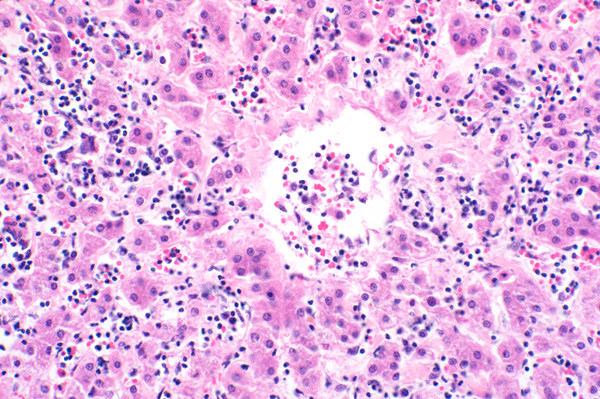

| 20x   |   Hematoxylin and Eosin | ||||

Centrilobular areas are expanded by increased subendothelial collagen (fibrosis).